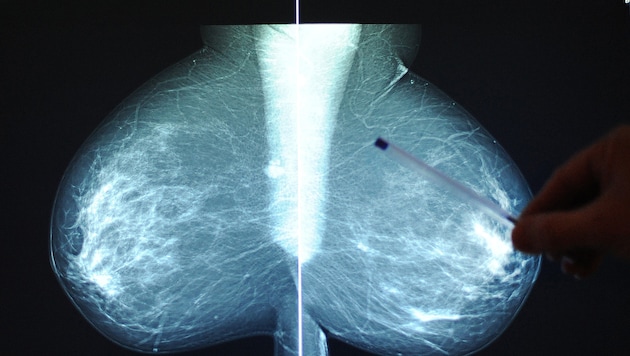

Mammografien sind die häufigsten bildgebenden Früherkennungsuntersuchungen – in diesem Fall auf Brustkrebs. Doch sie könnten durch neueste Forschungen noch einen bedeutenden Zusatznutzen erhalten: Warnungen vor Atherosklerose. Ein in den USA entwickeltes KI-System kann Verkalkungen in den Arterien der weiblichen Brust quantifizieren und auf mögliche Probleme hinweisen.

Im Fachmagazin der Europäischen Gesellschaft für Kardiologie (ESC; „European Heart Journal“) ist vor Kurzem eine wissenschaftliche Arbeit erschienen, welche die Bedeutung der Mammografie deutlich erhöhen könnte.

Bei Frauen oft nicht diagnostiziert

„Herz-Kreislauf-Erkrankungen werden bei Frauen häufig nicht diagnostiziert und unzureichend behandelt. Die automatische Quantifizierung der Brustarterienverkalkung (BAC) in der Screening-Mammografie kann Frauen mit einem erhöhten Risiko für Herz-Kreislauf-Erkrankungen identifizieren“, schrieben Theodorus Dapamede (Abteilung für Radiologie der Emory Universität in Atlanta/US-Bundesstaat Georgia) und seine Co-Autoren.

Die Wissenschafter werteten die Daten von 123.762 Frauen aus, die sich in zwei US-Gesundheitssystemen (Emory Healthcare und Mayo Clinic) Mammografie-Untersuchungen zur Brustkrebs-Früherkennung unterzogen hatten. Mit einem KI-unterstützten System wurden Verkalkungen der Arterien der untersuchten Brust quantifiziert und in vier Kategorien eingeteilt: keine Verkalkungen, leichte Verkalkungen (bis zehn Quadratmillimeter), mittelgradig (zehn bis 25 Quadratmillimeter) und schwer (mehr als 25 Quadratmillimeter).

Zusätzlicher Warnhinweis

Der Beobachtungszeitraum betrug sieben Jahre. In dieser Zeit wurden aufgetretene Herzinfarkte, Schlaganfälle, chronische Herzschwäche und Todesfälle infolge von Herzerkrankungen mit den Daten aus den Mammografien korreliert. Die akuten Ereignisse werden in der Fachsprache der Kardiologen als MACE – schwere Herz-Kreislauf-Ereignisse – zusammengefasst.

Die Ergebnisse sprechen dafür, dass eine Mammografie mit der Auswertung der atherosklerotischen Veränderungen in den Arterien der Brust einen zusätzlichen Hinweis auf ein Herz-Kreislauf-Risiko geben kann: Leichte Verkalkung bedeutete im Vergleich zu keinen Gefäßveränderungen ein um 28 bis 32 Prozent erhöhtes Risiko für solche potenziell lebensgefährlichen akuten Erkrankungen. Moderate Verkalkungen steigerten die Gefährdung bereits um 75 bis 79 Prozent. Schwere Verkalkung verdreifachte das Risiko.